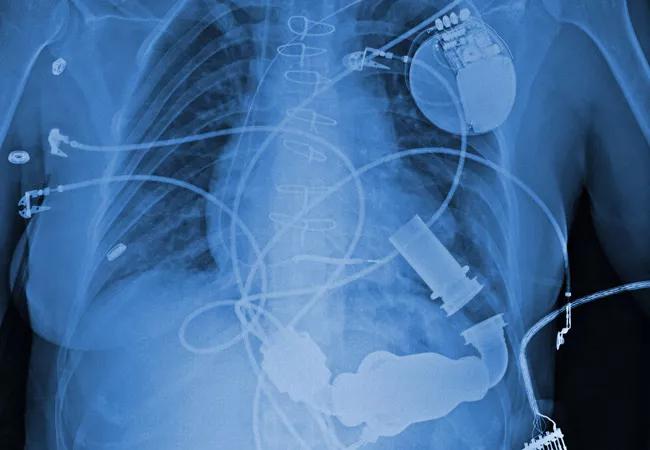

Use of an opioid-sparing regimen for postoperative pain management after left ventricular assist device (LVAD) implantation resulted in pain control comparable to that achieved with an opioid-based regimen while significantly reducing subsequent chronic opioid use.

The opioid-sparing regimen was associated with a significant decrease in need for opioid prescriptions at hospital discharge and with sustained freedom from chronic opioid use 18 months after surgery, reported Dmitry Yaranov, MD, a recent Cleveland Clinic advanced heart failure and transplant cardiology fellow who presented the results.

The study reviewed the charts of all 196 adult LVAD recipients at Cleveland Clinic from 2014 through 2017, comparing pain control and opioid use between those who received their LVADs before versus after Cleveland Clinic’s June 2016 adoption of an opioid-sparing regimen for LVAD patients.

A total of 196 patients received LVADs over the three-year study period. The sample was evenly divided between those receiving LVADs before (n = 98) and after (n = 98) adoption of the opioid-sparing regimen (OSR), and the before and after groups were statistically similar in all major patient characteristics, including age, sex, LVAD etiology, prior opioid use, baseline pain score, length of stay and others.